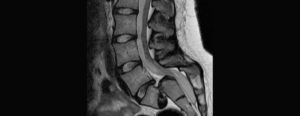

What is lumbar fusion?

We fuse the spine most commonly to stop excessive painful spinal movement at one or more levels of the spine.

Metal work (typically rods and screws) are used to hold the spine together allowing the spine to fuse.

We fuse the spine for several different reasons including spinal instability or deformity (spondylolisthesis or scoliosis) where other simpler conservative treatments have not worked.

What is the procedure for lumbar fusion?

We can fuse the spine in different ways, accessing your spine from the front, side, or back. Our options depend on the level of the spine being fused and the problem being treated.

The most versatile and commonly performed fusion is through the skin of the back (posterior).

We specialise in minimally invasive techniques to reduce damage to the muscles.

Typically we place titanium screws into the spine and connect these with a strong metal rod which holds everything securely.

Sometimes it is helpful to remove the disc and replace this with a block of material (called a cage). This may provide more support to the spine and helps us to correct a spinal deformity better.

We use a combination of your own bone (from the site of the operation) and synthetic bone graft to encourage the spine to fuse together. Fusion between the bones will prevent any further movement at the treated level.